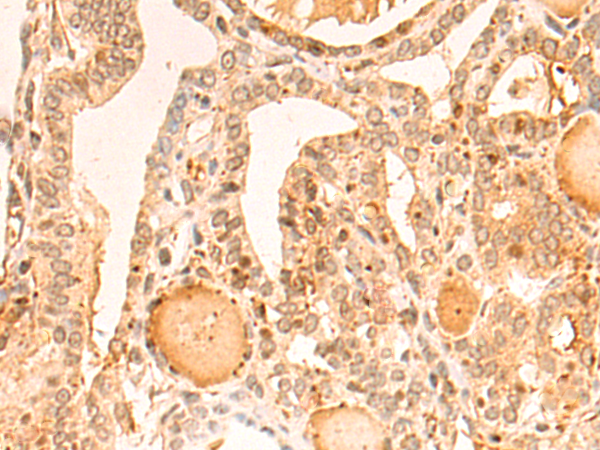

分类: 科研抗体货号: P13256别名: GT24; NPRAP应用: IHC反应种属: Human, Mouse